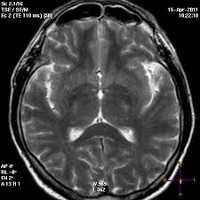

Может применяться компьютерная томография (КТ) и магнитно-резонансная томография (МРТ). С помощью КТ определяют участки пониженной плотности в центральном сером веществе среднего мозга и в части таламуса, но в большинстве случаев этот метод не выявляет очаговой патологии при острой энцефалопатии.

Наиболее эффективный метод диагностики энцефалопатии Вернике — это МРТ. Интерпретировать результаты МРТ сможет только врач.